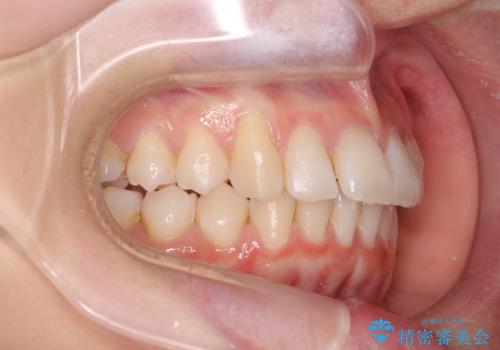

歯を抜かないで出っ歯を治したい

- 前歯が出ていることを主訴に来院。

歯を抜かずにマウスピース矯正をご希望でした。

歯と歯の間をわずかに削り、歯並びを少し横に拡大して並べました。

奥にすき間がなかったため後ろには下げていません。

沢山ひっこめるには4本抜歯でワイヤーの選択肢もありましたが、抜かないでできる範囲をご希望されました。

とがった形の歯列を整えるだけでもだいぶ印象は変わると思います。

今回歯列を広げた結果、上顎犬歯の歯肉は多少退縮しています。